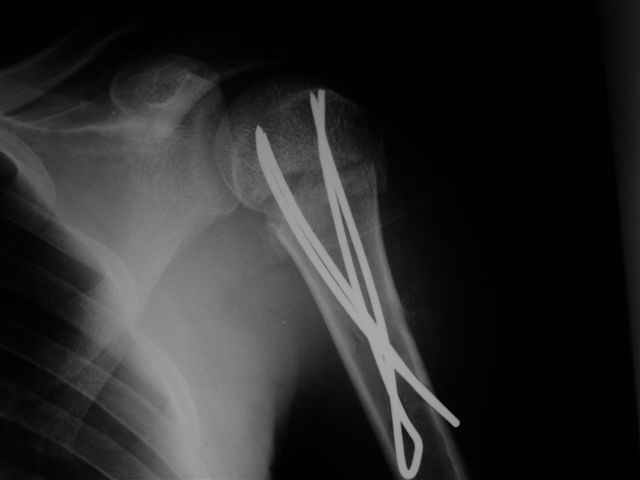

Здесь случай перелома-вывиха плеча, больному 56 лет, после "дважды" закрытой неудачной репозиции, опять же ургентно взяли в операционную, после полного общего обезболивания попытались сделать репозицию, и фиксацию провели спицами.

Больной находился в повязке, примерно напоминяющей косыночную, рекомендованы движения в локтевом суставе и маятниковые движения в плече, спицы удалены в три недели (были случаи миграции)

Больной амбулаторный, предупрежден на случай осложнения АВН головки.

Клинические снимки - 3 недели после операции